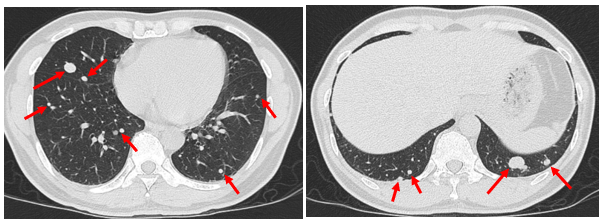

Hình ảnh Cắt lớp vi tính lồng ngực (04/2023):

Hình 6: Hình ảnh nhiều nốt mờ rải rác ở nhu mô 2 phổi, nốt lớn nhất có đường kính 9 mm (mũi tên đỏ). Số lượng tổn thương giảm so với CT 6/2022.